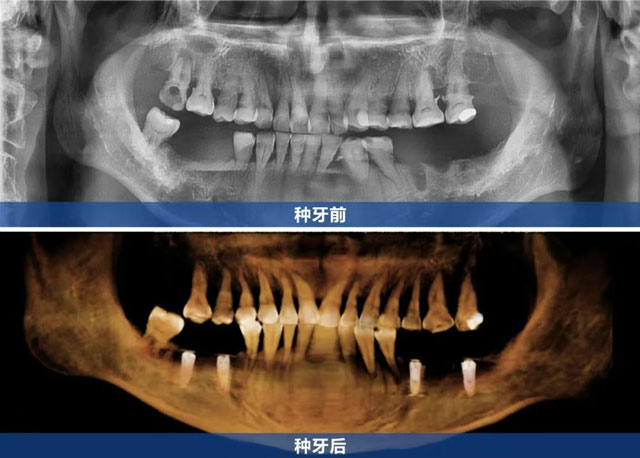

新橋口腔自貢院區(qū)的林麗醫(yī)生接診后,以專業(yè)嚴(yán)謹(jǐn)?shù)膽B(tài)度為劉叔叔進行了全面細(xì)致的檢查。通過CBCT檢查、口內(nèi)檢查及詳細(xì)問診,林麗醫(yī)生明確了劉叔叔的缺牙情況,為其定制了多顆種植修復(fù)方案,計劃通過4顆種植牙幫助劉叔叔重建咀嚼功能。